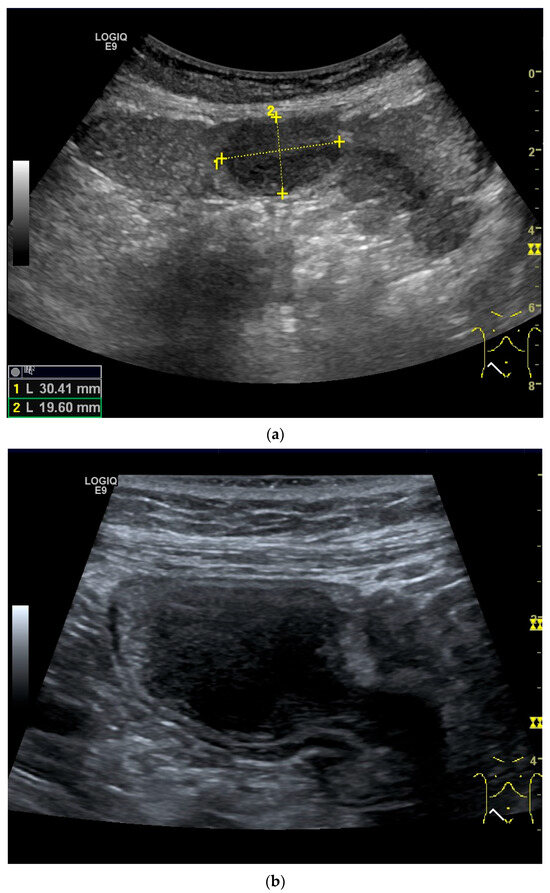

Figure 11.

GIST. A 30 mm large, very hypoechoic, almost anechoic round mass is visible in the left upper abdomen. This is located in the jejunum; the wall (W) and lumen (L) are visible (a). Macro vessels can be distinguished on Power Doppler, demonstrating that the lesion is solid and not cystic (b). On CEUS with 2.4 mL SonoVue (linear transducer 9 MHz), a small wheel-spoke-like vascular branching is visible at the margin (arrow) (c) with centrifugal enhancement (arrow) (d). Hyperenhancement is heterogeneous in the early arterial phase (e,f) and becomes homogeneous in the later course of the arterial phase (g). The extent of the heterogeneously enhanced tumor is marked with arrows (e). The intensity of the enhancement decreases during the first minute. The tumor is marked with arrows (h). Jejunal segment resection revealed the histology of an epithelioid GIST.